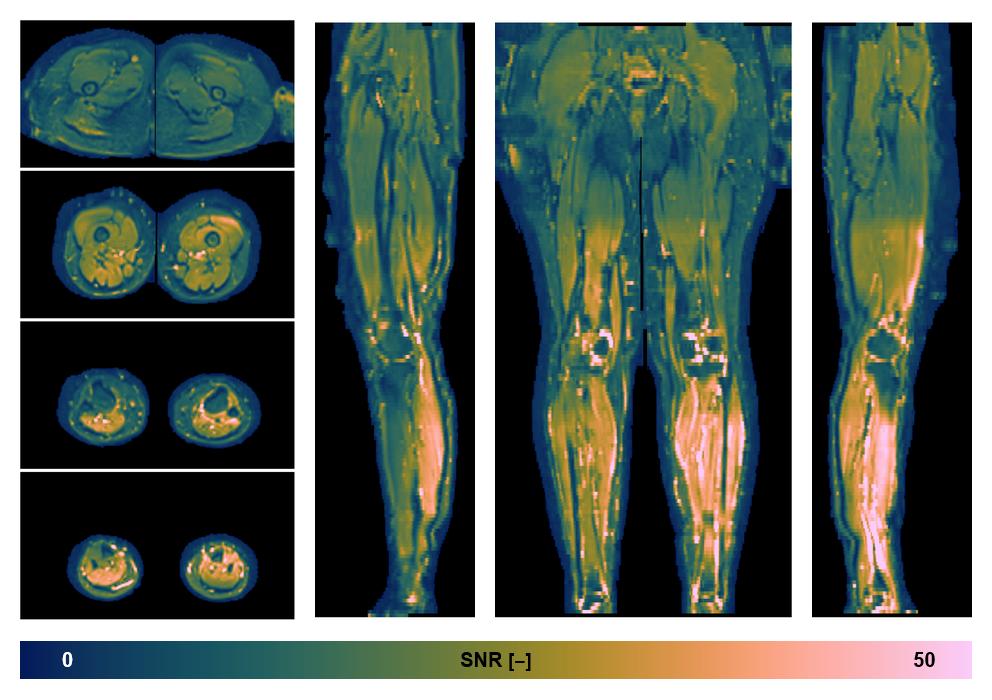

• SNR distribution

The SNR distribution of the dixon data.